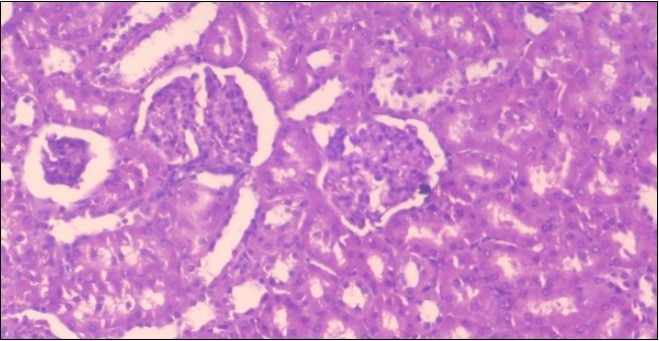

The histological examination of the kidney of the control rats fed on a standard diet showing normal rounded capsules with normal Bowman's glomeruli, round proximal tubules and elongated distal tubules with high cuboidal cells figure 1. The rats fed (HFD) showed fatty degeneration of the tubules with eosinophilic material deposition, glomerular atrophy with wide urinary space and distal tubules with extrusion of nuclei into lumen figure 2. By comparison kidneys of rats which were treated by fennel after being obese and the control rats observed partial improvement in both Bowman's capsules and proximal tubules. Note the distal tubules show less focal fatty infiltration figure 3.While examination of rats kidney that were treated by ator after obesity showed improvement in Bowman's capsules with normal glomerular and partial improvement in proximal tubules and distal tubules, figure 4. Kidney of rats that were treated by fennel and ator after obesity and the control rats showed high improvement in the tissues with normal glomerular and that Most of Bowman's capsules and renal tubules, restoring their normal appearance figure 5.

Figure 4.Photomicrogragh of kidney section of treated rat with Ator drug showing improvement in Bowman's capsules with normal glomerular and partial improvement in proximal tubules and distal tubules, (H&E) (40X).

Photomicrogragh of kidney section of treated rat with Ator drug showing improvement in                                  Bowman's capsules with normal  glomerular and partial                     improvement in proximal tubules  and distal tubules,  (H&E) (40X).